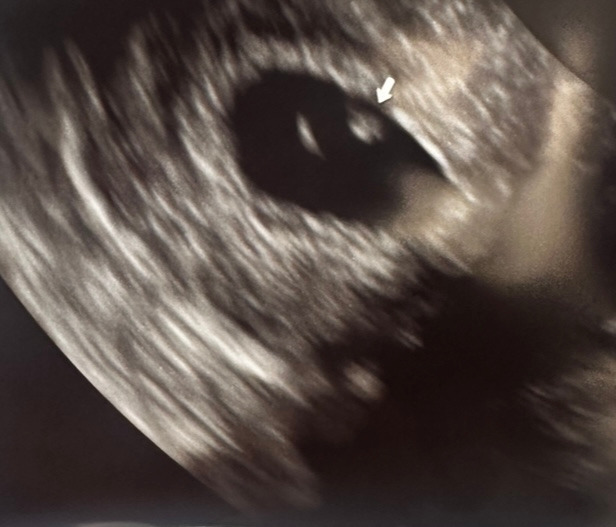

드디어 아기집을 확인하였다.

엄마의 걱정을 날려버리듯 아주 잘 자리 잡은 아기집.